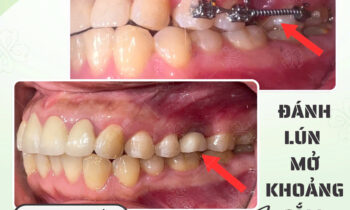

Hoàn thành 1 quá trình niềng răng đổi lại kết quả như này thật sự xứng đáng đúng không cả nhà???? ❌Bạn sẽ thấy khuôn mặt mình mất cân đối khi gặp tình trạng răng móm, hô, lệch,…khiến bạn cảm thấy tự ti khi cười với người đối diện. ????Tuy nhiên, nhờ vào phương pháp…